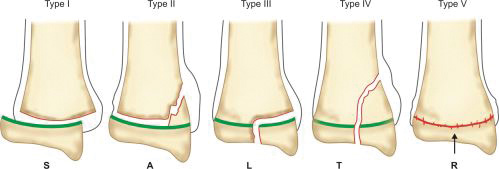

Physeal injury: Open physes are susceptible to injury in children. Theses are common injuries in children especially in adolescents (12–14 years) nearing the growth spurts. Most common site of physeal injury is phalanx followed by distal radius. Salter Harris classification (Table 1.7) (Fig. 1.24) is most commonly used to classify physeal injuries in children. It is based on the location of fracture in one or more of epiphysis, physis and metaphysis. It also predicts the outcome/prognosis. Type I has the best and type V has the worst prognosis.

Mnemonic SALTR is useful in remembering this classification (Table 1.8).

Diagnosis of physeal injuries: Child presents with pain and swelling around the joint. Diagnosis of physeal injuries can be made on routine X-rays (Fig. 1.25). Whenever in doubt comparison with X-ray views of normal joint and MRI are very useful.

Treatment: In children fractures heal at a faster rate so timely reduction of physeal injuries is of paramount -importance. Attempt of reduction in cases presenting late can further damage the growth plate. In type I and II fractures reduction should not be attempted after 7–10 days, however type III and type IV fractures must be reduced as they involve the articular cartilage. Once reduced reduction can be secured with pins or/and cast.

Complications: Growth disturbance (angular deformity, shortening) is the single most important complication of physeal injury. Significant deformity may require osteotomy and/or limb lengthening procedures.